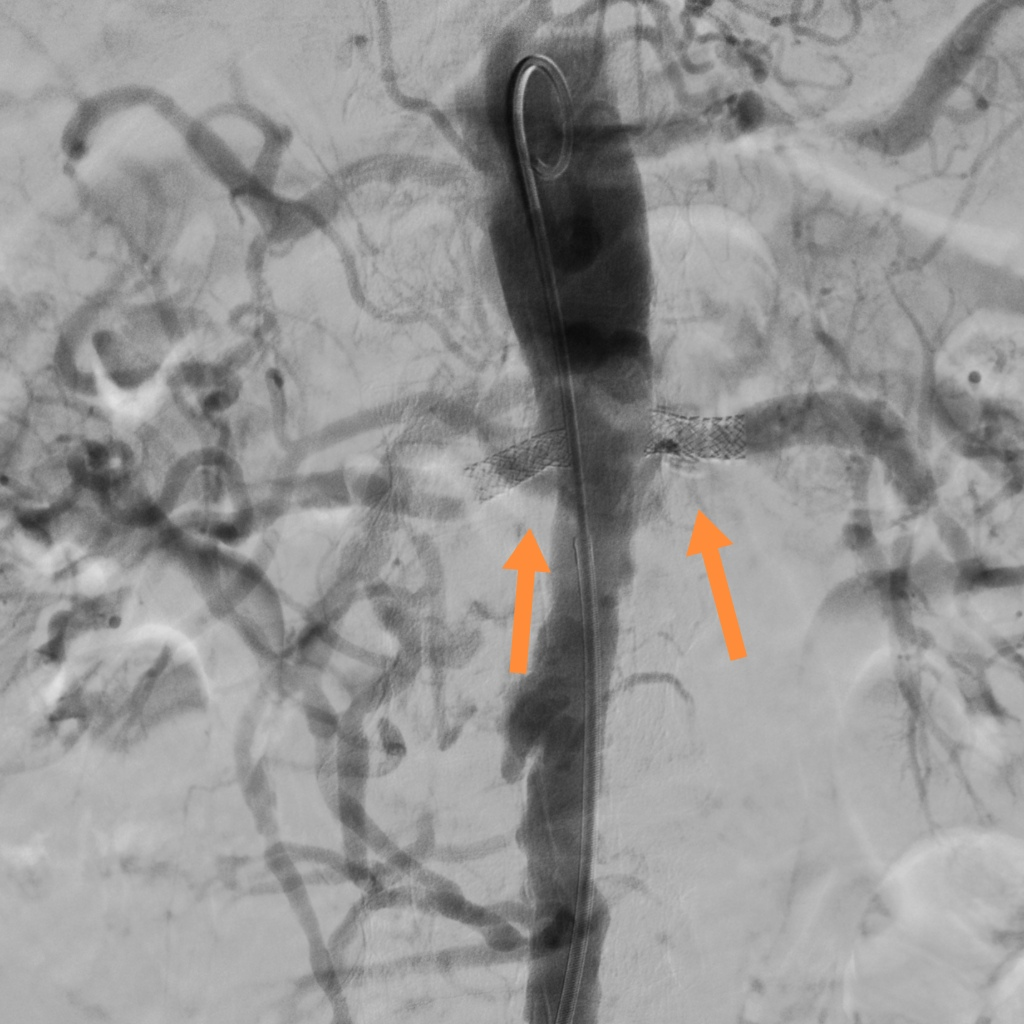

注:DSA下双侧肾动脉重度狭窄;

注:支架置入术后肾动脉管腔通畅